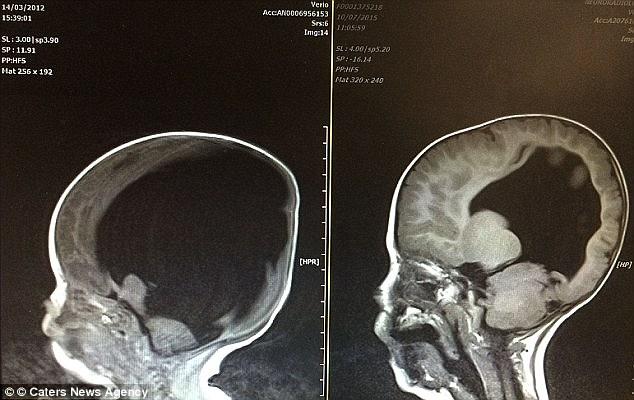

La naștere, Noah avea doar 2% din creier. Părinților li s-a spus să își ia la revedere de la el, pentru că șansele ca el să supraviețuiască mai mult de câteva zile erau aproape zero.

Doar că bebelușul a crescut și a crescut și a crescut! Când avea 3 ani, o tomografie a arătat că avusese loc un miracol, creierul lui Noah se dezvoltase, ajungând la 80% din capacitatea maximă.